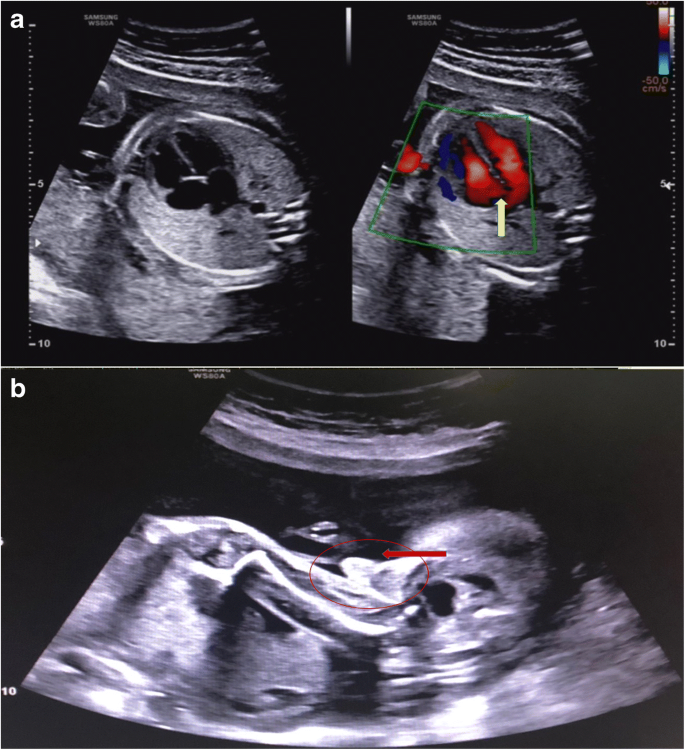

Fig. 4

figure 4

Ultrasound examination results of case 18. (a) Ultrasound results suggest tricuspid regurgitation. (b) The maleness of the fetus was confirmed at 24 weeks

In addition, prenatal diagnosis confirmed 9 copy number variation (CNV) cases (Table 4). For all CNV cases, the fetal fragment fraction was 10.6–28.8%. The Z score of the X chromosome in NIPT was − 2.562 to − 17.657. Interestingly, case 18 was suspected to have X/XY mosaicism by NIPT, and CMA confirmed the large segments of deletion and duplication of the sex chromosome, including the Y chromosome, which had a 13.7 Mb deletion and the X chromosome had a 4.1 Mb duplication (Fig. 3). The fetus was confirmed as male at 24 weeks by ultrasound examination and the ultrasound results also suggested tricuspid regurgitation (Fig. 4). All of the CNV cases chose to terminate the pregnancy. Case 21 chose to terminate the pregnancy and agreed to a fetal autopsy. The autopsy results confirmed tissue degeneration.